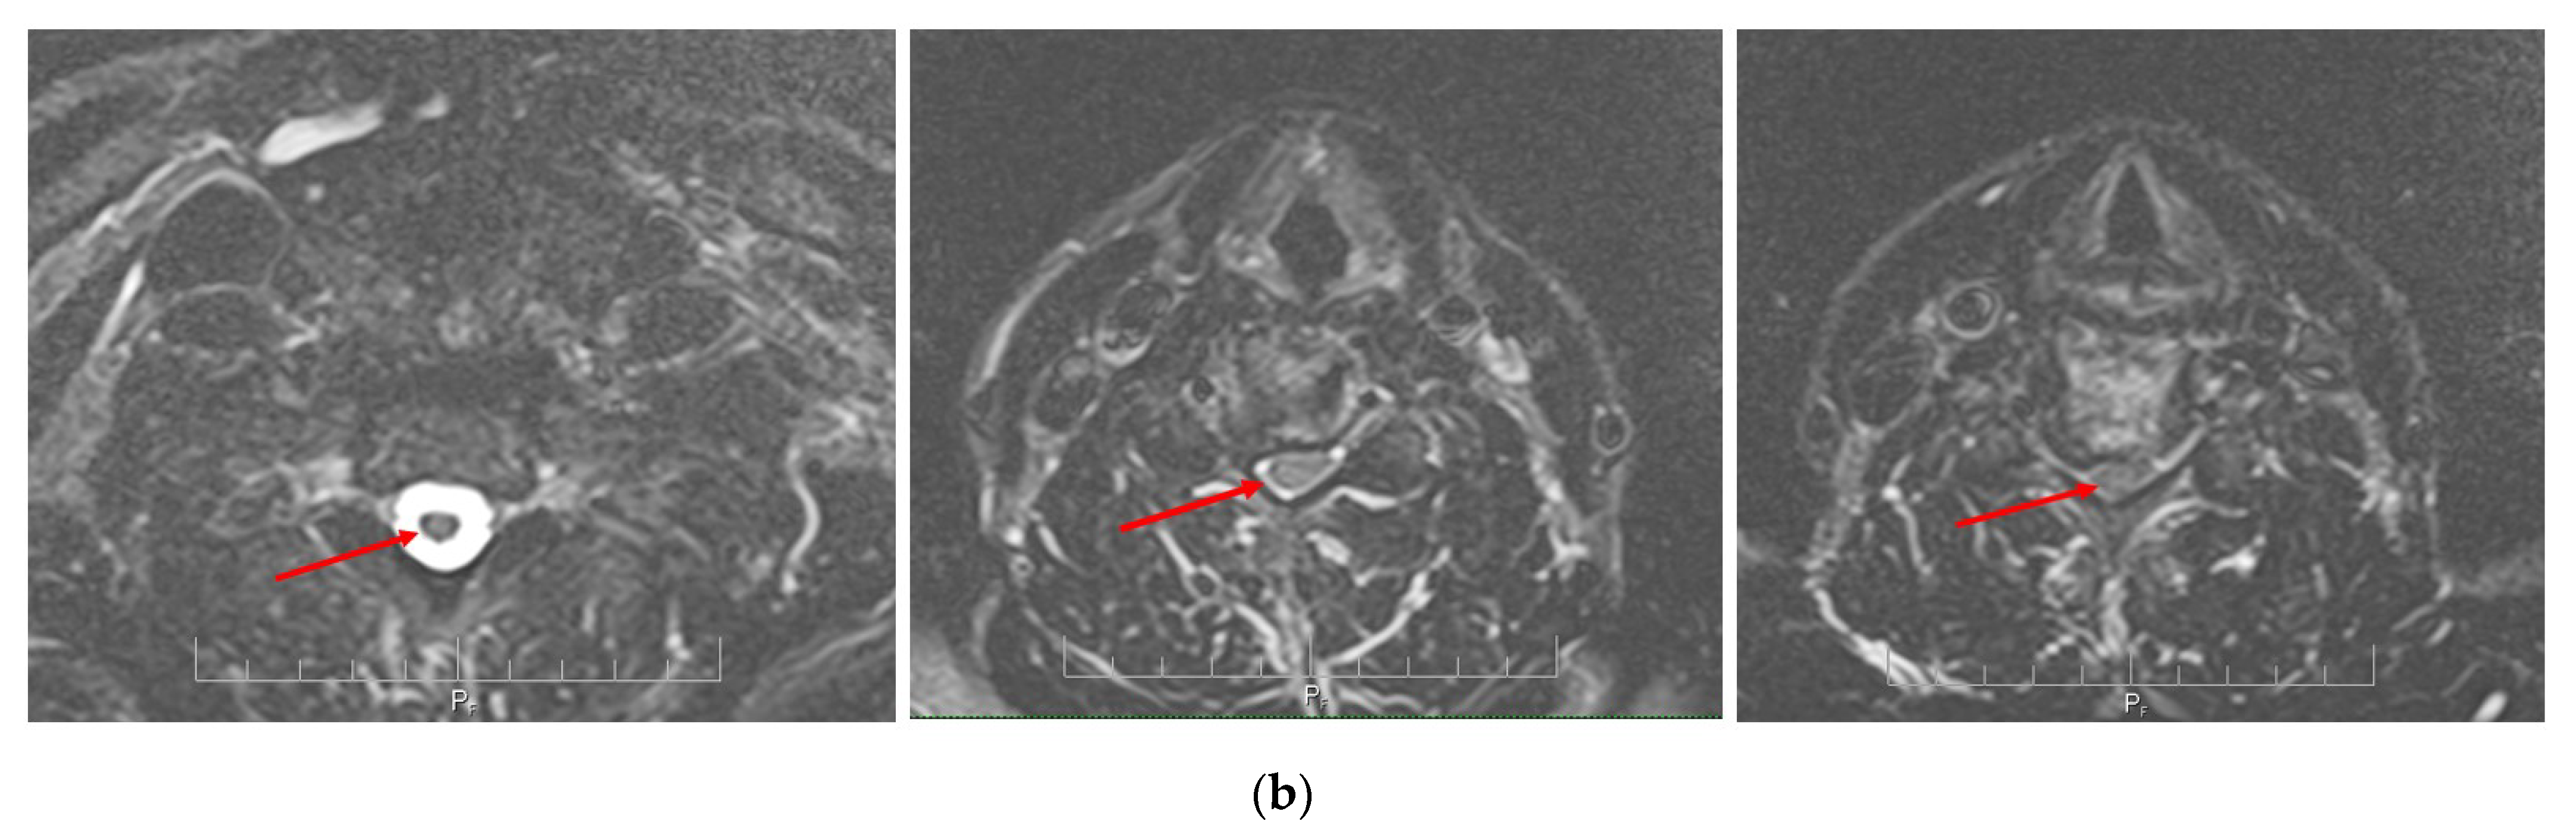

2.4. Neuroimaging